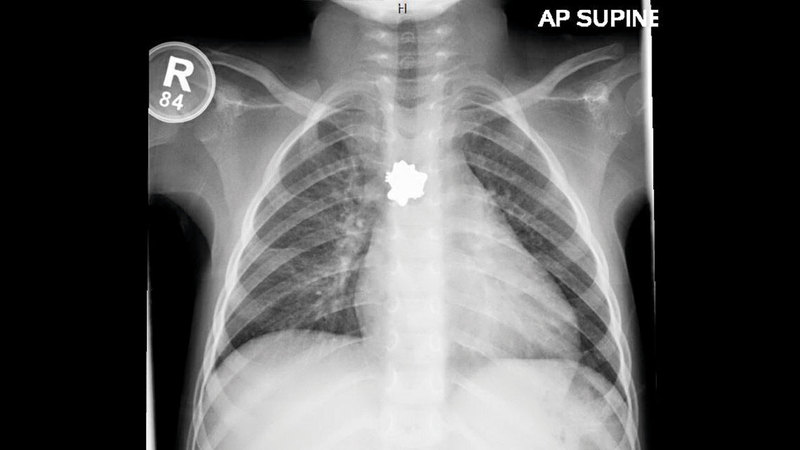

استخرج فريق طبي في مدينة الشيخ خليفة الطبية قرطاً (حلق) ذا حواف متعرجة، على شكل الشخصية الكرتونية «هلو كيتي»، من معدة طفلة مواطنة، قالت والدتها إنها حصلت عليه من أحد الأدراج، وابتلعته. وأضافت أن ابنتها شعرت بألم وضيق شديد في التنفس، ودخلت في نوبة بكاء مستمر.

وأفاد استشاري الجهاز الهضمي للأطفال في مدينة الشيخ خليفة الطبية، الدكتور ديفيد راوت، بأن المستشفى استقبل الطفلة، البالغة ثلاث سنوات، بعد ابتلاعها قرطاً من الذهب، استقر في جهازها الهضمي.